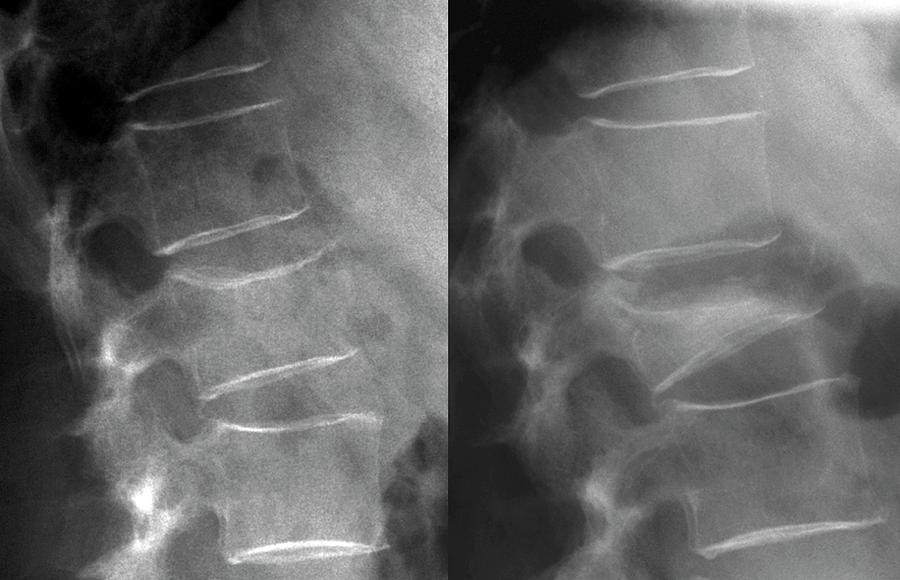

A fratura na coluna vertebral causada pela osteoporose exige cuidados e pode, em alguns casos, passar despercebida. No entanto, os prejuízos ao paciente acometido por essa fratura são inúmeros e podem impactar diretamente em sua qualidade de vida.

Atualmente, além da vertebroplastia e da cifoplastia, uma nova técnica minimamente invasiva permite a recuperação total do paciente, em menor tempo. O procedimento corrige a altura vertebral por meio de um dispositivo que sustenta a vértebra fraturada.